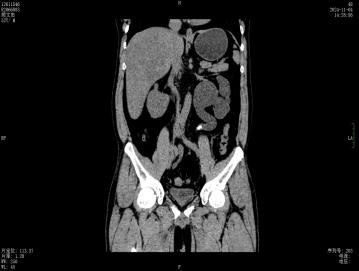

今年8月起,左腰部酸胀频繁不适,这才想起医生曾经的叮嘱,后找到深圳市罗湖区人民泌尿外科姜刚刚副主任医生门诊就诊,行CT检查发现整个左肾重度积水,而结石仍旧卡在输尿管内,最终只能无奈手术切除没有功能的左肾。